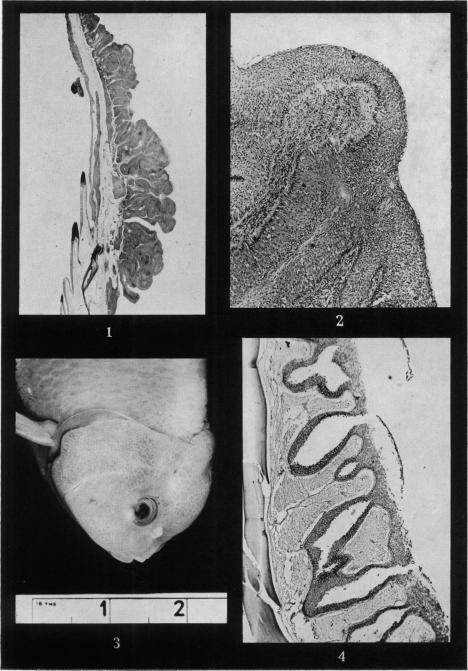

Hormonally induced epithelial hyperplasia in the goldfish (Carrasius auratus).

Br J Cancer. 1952 Sep;6(3):246-8. doi: 10.1038/bjc.1952.28.